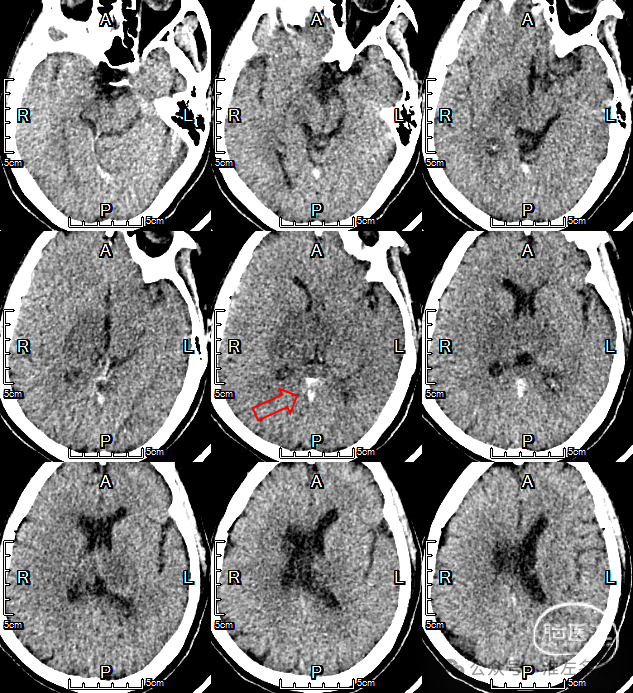

急诊多模式CT

2024-9-23 07:50

CT平扫:双侧丘脑低密度肿胀,直窦-大脑大静脉血栓高密度。

CT平扫(矢状位薄层重建):直窦-大脑大静脉-大脑内静脉-下矢状窦急性血栓高密度征。

CTV:左侧横窦-乙状窦细小,右侧横窦充盈缺损,深部静脉系统未见显影,上矢状窦显影不清晰。